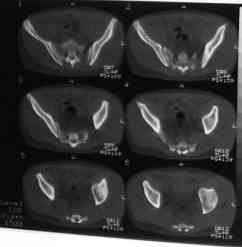

Уважаемые коллеги! На днях оперировал перелом таза месячной давности - разрыв симфиза, перелом обеих ветвей правой лонной кости, трансфораминальный перелом крестца слева. Представляю рентгенограммы с задержкой - технические причины.

Предоперационные рентген и КТ, в операционной - снимки после каждого фиксатора. Вертикальное смещение полностью устранить не удалось. В первую очередь за счет заднего полукольца. Хотя при компрессии на стержнях горизонтальное смещение было сантиметра 1,5. Т.е. крестец, на мой взгляд еще не сросся. От коллег хотел-бы услышать допустима-ли такая остаточная деформация?